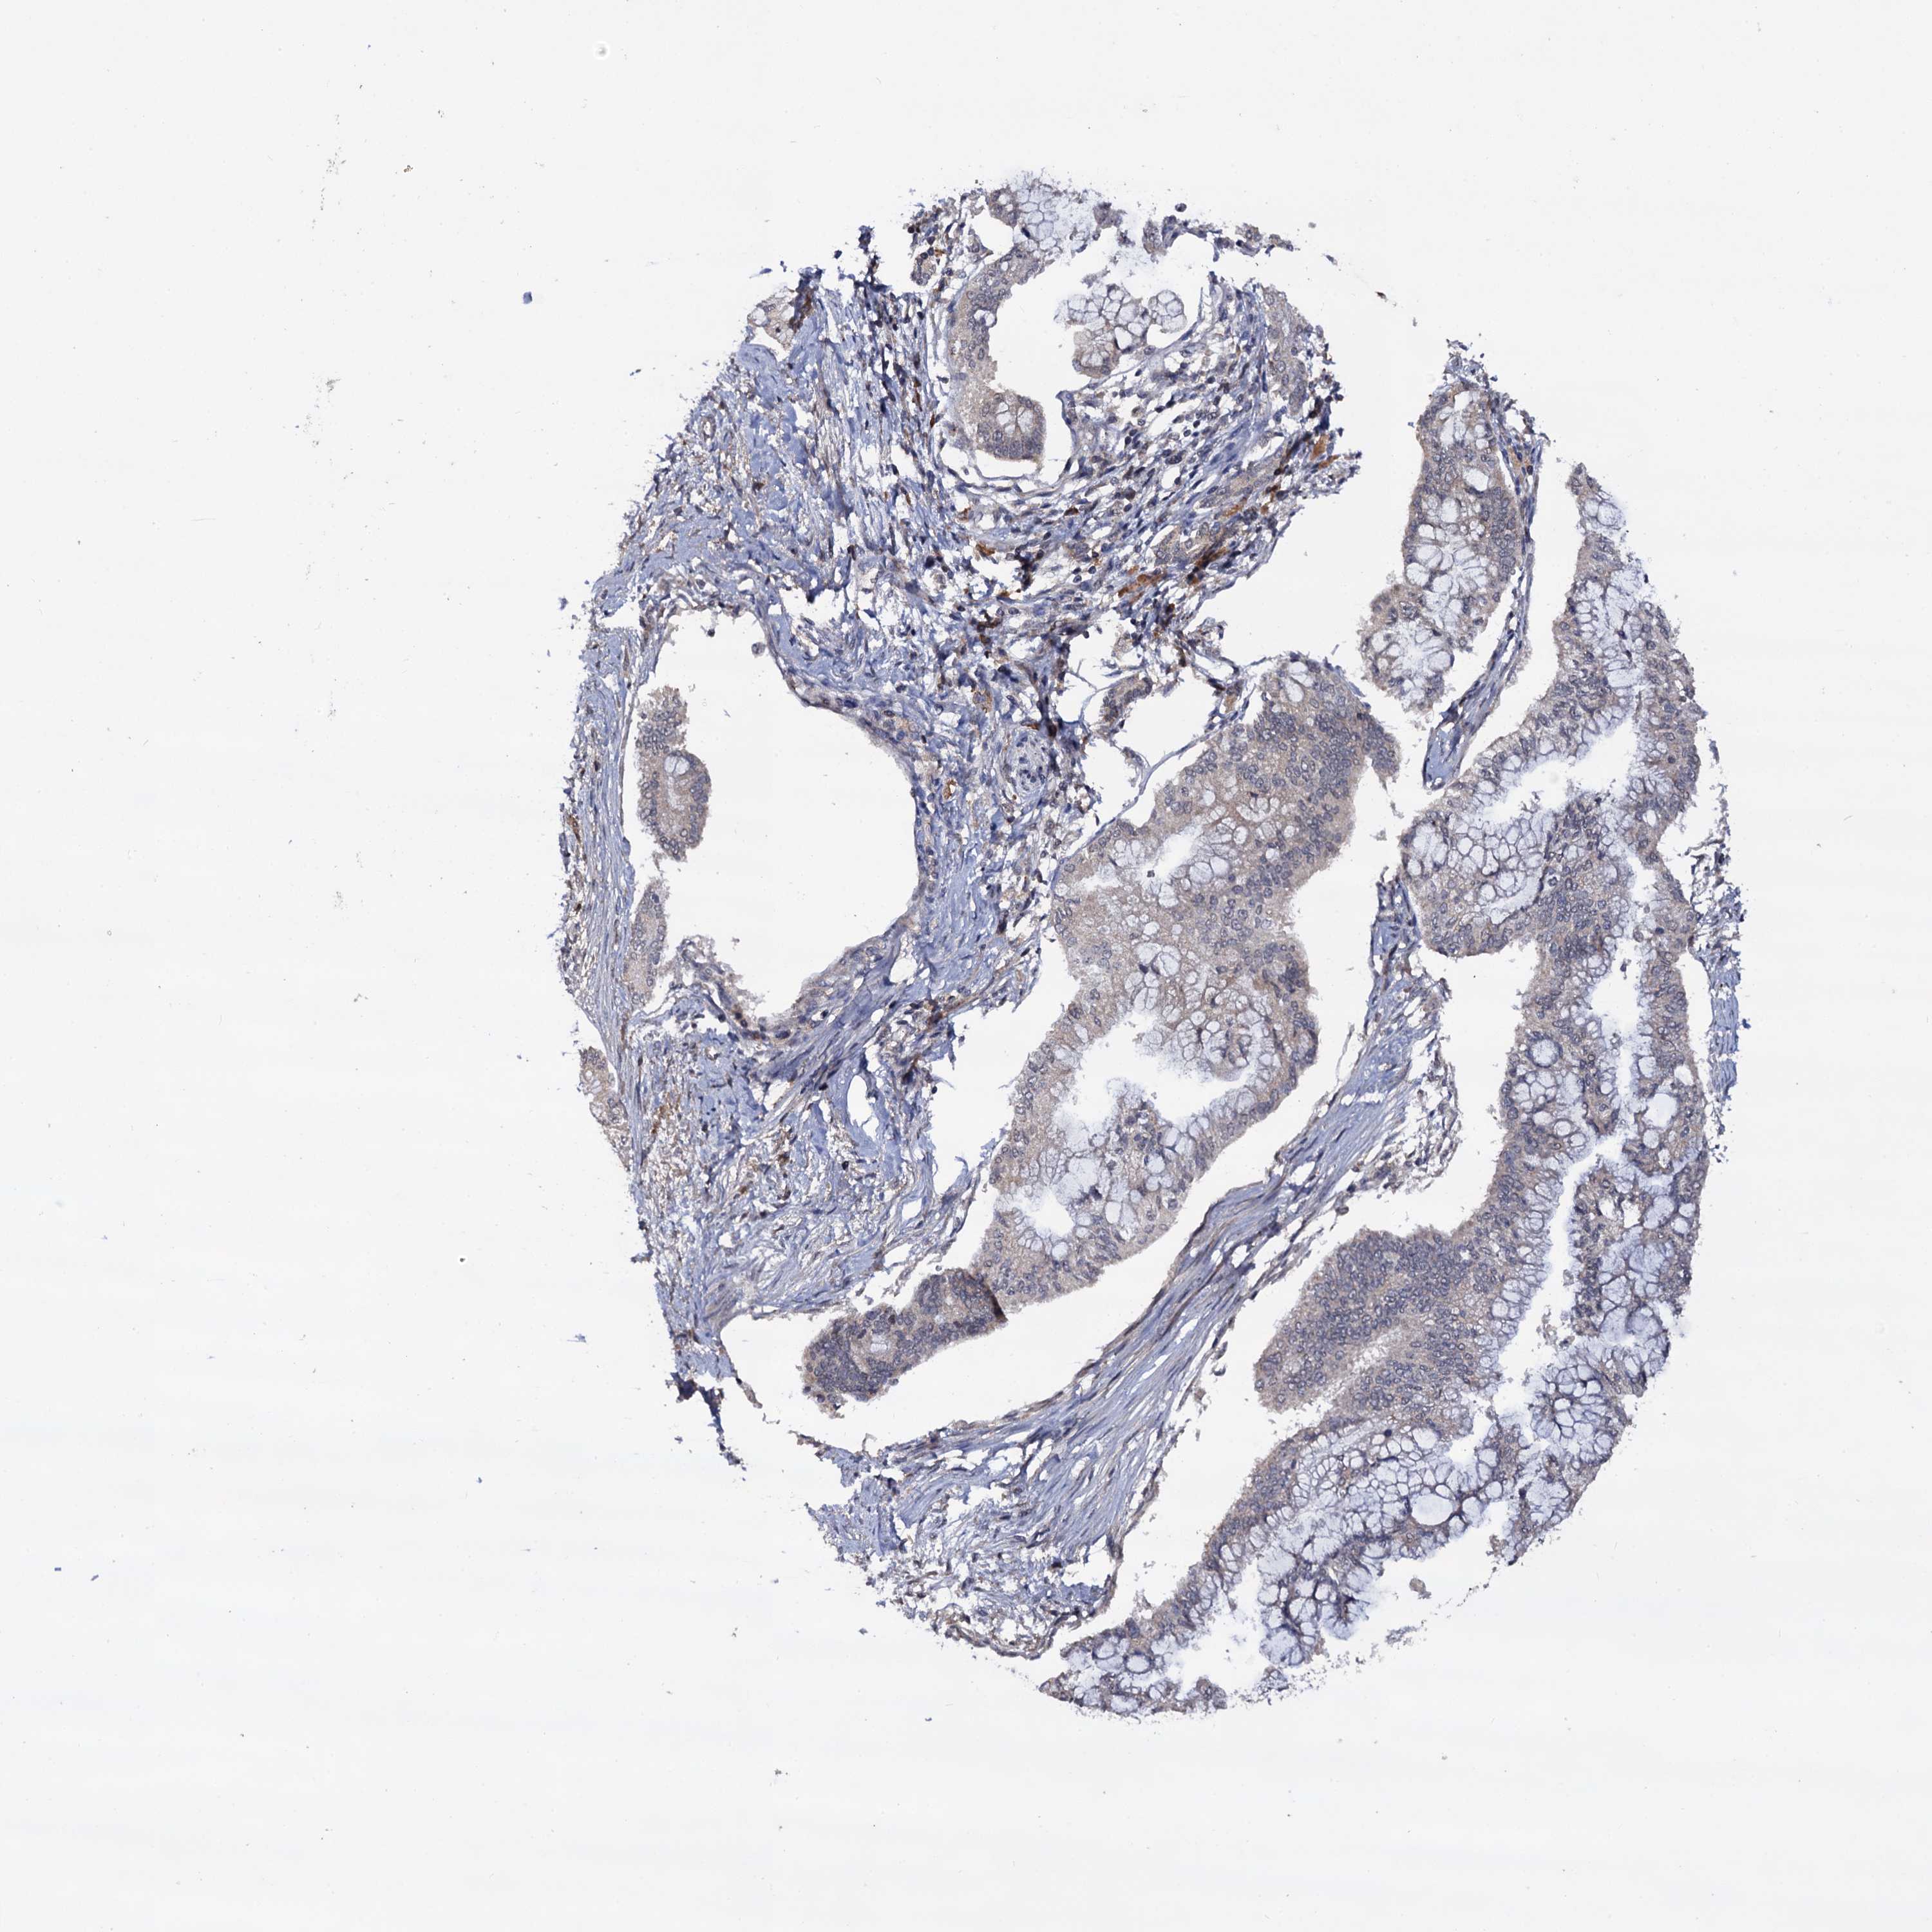

PANCREATIC CANCER - Protein expressioni

A mouse-over function shows sample information and annotation data. Click on an image to view it in a full screen mode. Samples can be filtered based on level of antibody staining by selecting one or several of the following categories: high, medium, low and not detected. The assay and annotation is described here.

Note that samples used for immunohistochemistry by the Human Protein Atlas do not correspond to samples in the TCGA dataset.

Antibody stainingi

Antibody staining in the annotated cell types in the current human tissue is reported as not detected, low, medium, or high, based on conventional immunohistochemistry profiling in selected tissues. This score is based on the combination of the staining intensity and fraction of stained cells.

Each image is clickable and will lead to virtual microscopy that enables deeper exploration of all samples and also displays staining intensity scores, fraction scores and subcellular localization as well as patient and tissue information for each sample.

Antibody HPA039318

Antibody HPA039763

Staining

High

Medium

Low

Not detected

Intensity

Strong

Moderate

Weak

Negative

Quantity

>75%

75%-25%

<25%

None

Location

Nuclear

Cytoplasmic/membranous

Cytoplasmic/membranous,nuclear

Adenocarcinoma, NOS